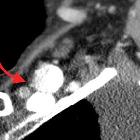

Subclavian

vein aneurysm - Case presentation and discussion. Venography of the left subclavian vein after endovascular therapy with coils within the aneurysm. Complete exclusion of aneurysm from the venous circulation and patency of the veins is observed.

vein aneurysm - Case presentation and discussion. Power Doppler demonstrates irregular echogenic image which generates acoustic shadowing, corresponding to embolisation material within the aneurysm. There is adequate bloodflow within the subclavian vein.

vein aneurysm - Case presentation and discussion. Spectral Doppler demonstrates adequate bloodflow within the subclavian vein.